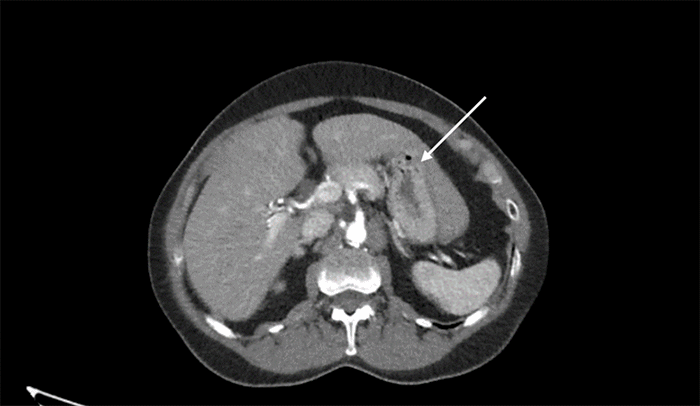

In light of a recent hospitalization for oropharyngeal bleeding, clopidogrel was held for 5-7 days pre-procedure to minimize periprocedural bleeding risks. Preoperative imaging from prior revascularization identified a complex abdominal anatomy: the liver extended beyond the midline and overlapped the stomach anteriorly, limiting the suitable area for gastrostomy tube placement (Figure 1). To mitigate the potential for liver injury during the procedure, the team opted for ultrasound guidance following a collaborative discussion with anesthesia.

Figure 1. Preoperative CT Angiography Demonstrating Aorto-iliofemoral Runoff: Extensive Hepatic Coverage of Stomach. Published with Permission

The arrow denotes a significant portion of the stomach covered by the liver